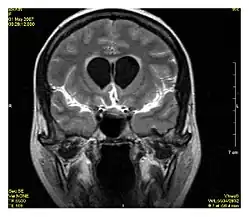

La recuperación de la inversión atenuada de fluido (FLAIR, del inglés: FLuid-Attenuated Inversion Recovery) es una secuencia de resonancia magnética con una recuperación de la inversión que neutraliza los fluidos. Por ejemplo, se puede usar en imágenes cerebrales para suprimir los efectos del líquido cefalorraquídeo (LCR) con el fin de resaltar las lesiones hiperintensas periventriculares, como las placas de esclerosis múltiple (EM).[1] Esta secuencia fue desarrollada por el Dr. Graeme Bydder. Puede usarse tanto con imágenes tridimensionales (3D FLAIR) como bidimensionales (2D FLAIR).

El análisis de secuencia FLAIR resulta especialmente útil en la evaluación y estudio de determinadas alteraciones como:

- Infartos lacunares

- Placas de esclerosis múltiple

- Hemorragia subaracnoidea

- Traumatismo craneoencefálico

- Meningitis y otras enfermedades leptomeníngeas*